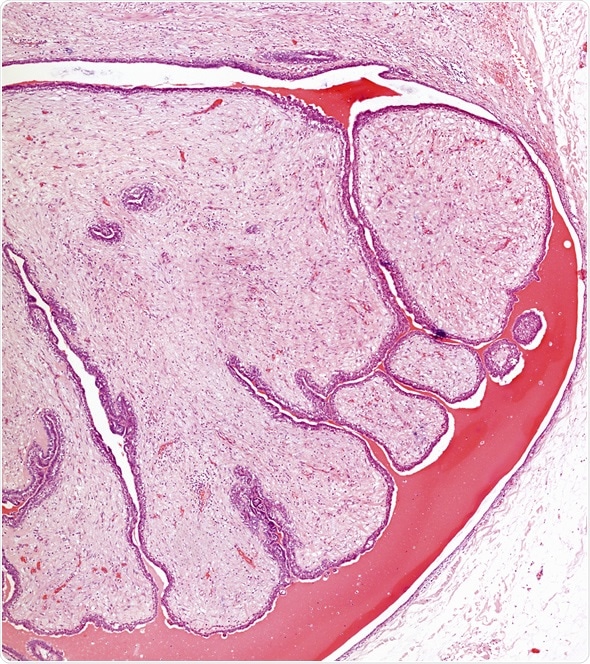

Microscope picture of fibroadenoma of the breast - Image Copyright: Convit / Shutterstock

A presence of customary ductal hyperplasia within the fibroadenoma can result in the presence of larger branched proliferative epithelial clusters in the aspirates. Corresponding histology shows intra-canalicular and peri-canalicular growth pattern.